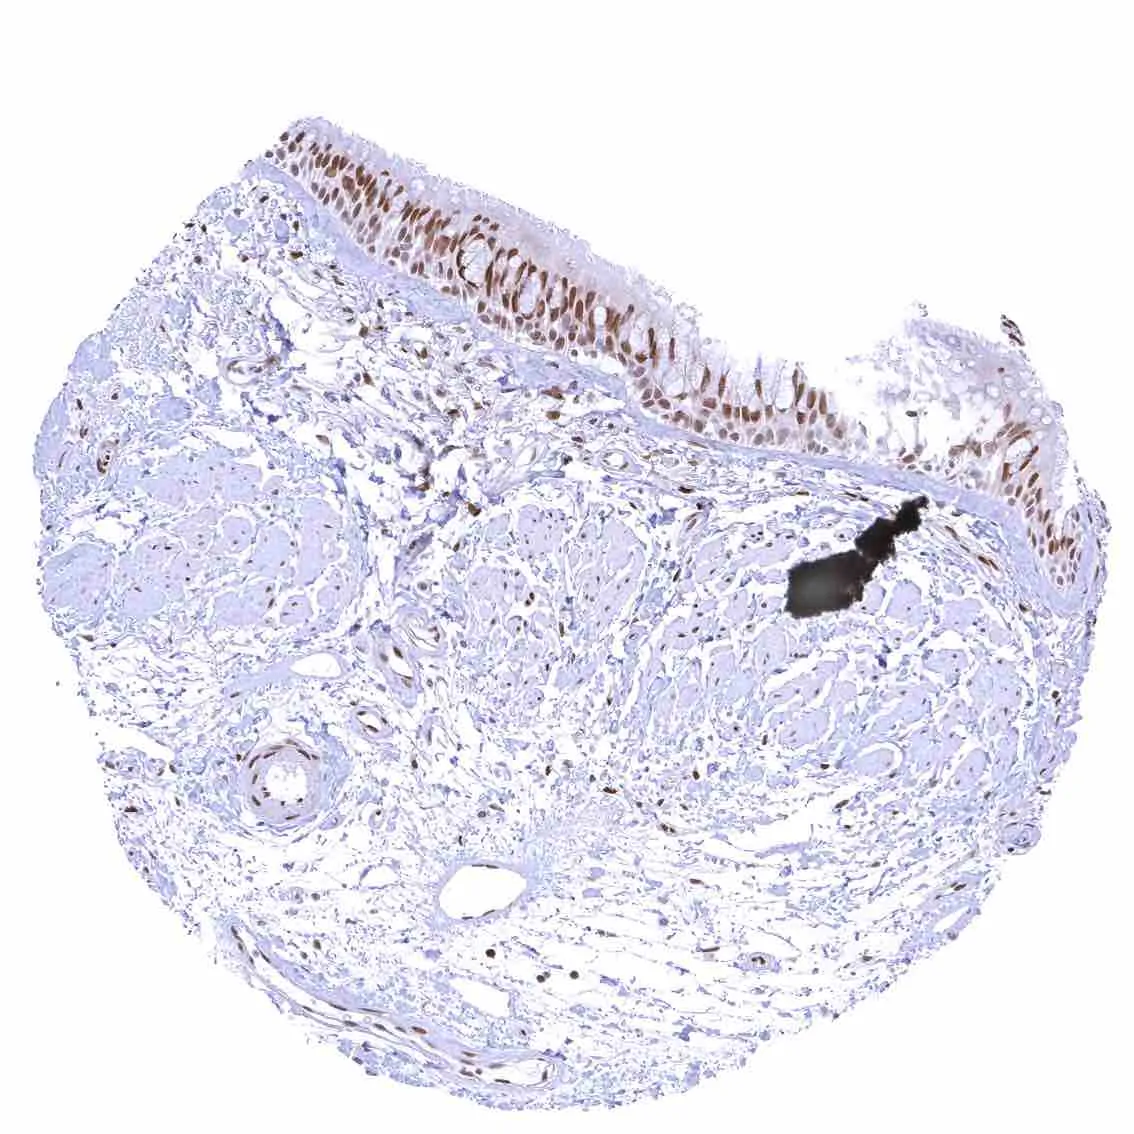

Stomach, corpus – Nuclear p27 positivity predominates in superficial epithelial cells and is rarely seen in neck cells.